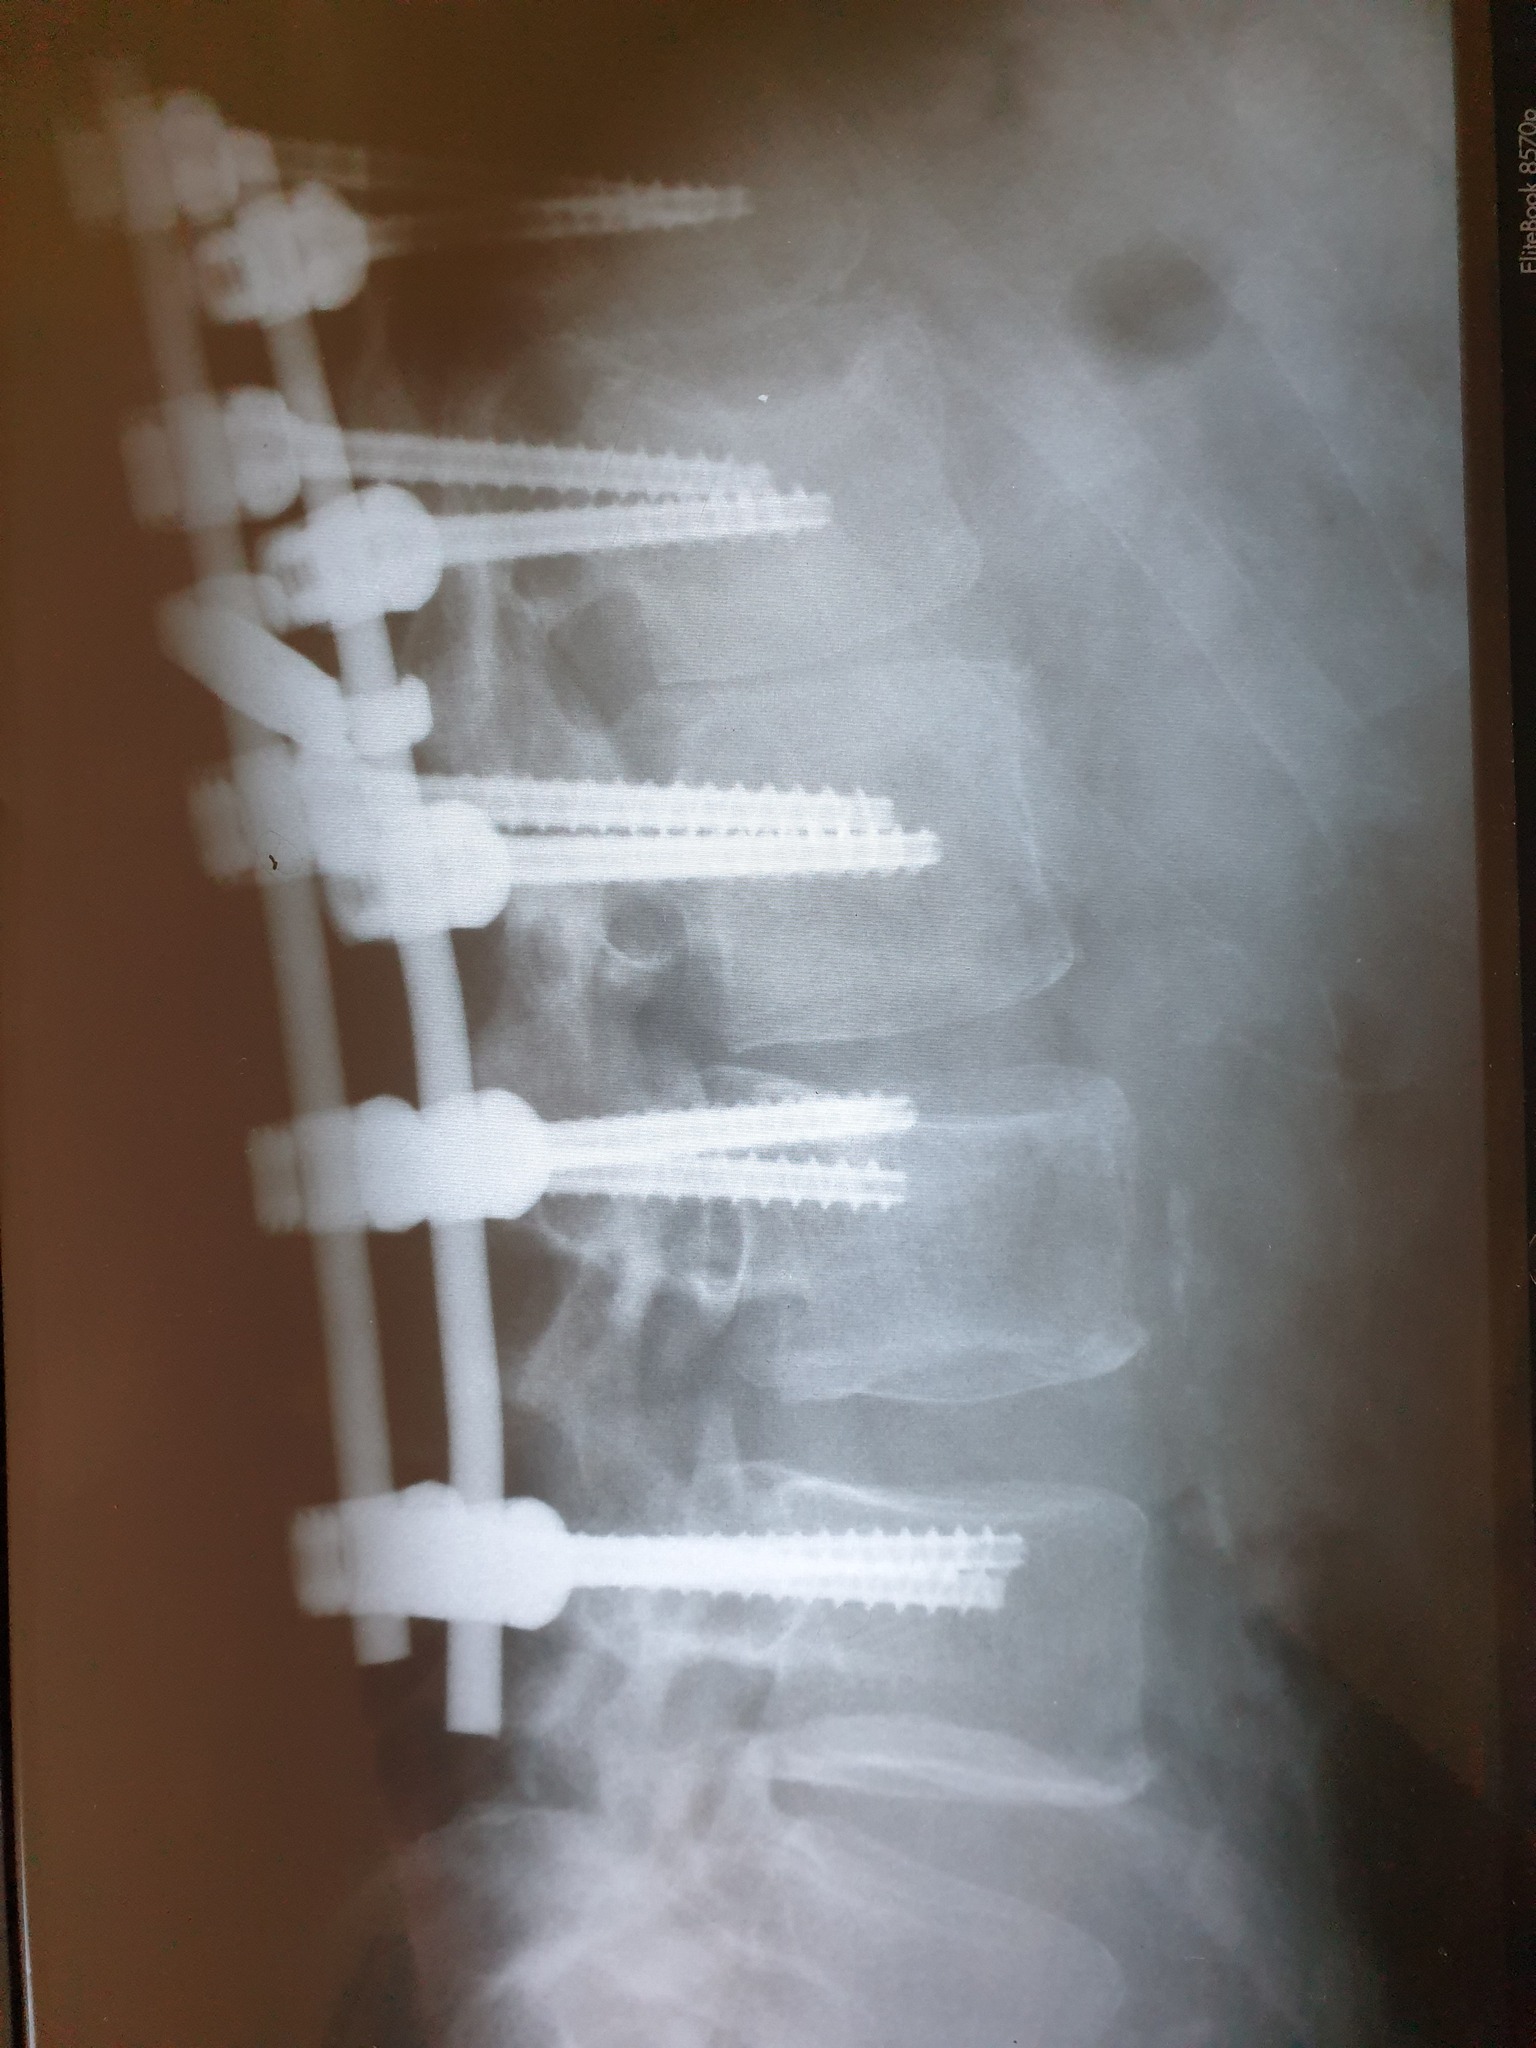

Nakon što je 11. februara doživio povredu na radnom mjestu, tačnije nakon što je pao sa lotri i slomio kičmu na dva mjesta Nino Katić je odlučio da progovori i sa svima podijeli svoje iskustvo, ali i pokaže zastrašujuće povrede koje je zadobio.

– Šta dobiješ u “Centrumu” kada zbog njihovog neispravnog sredstva za rad slomiš kičmu na dva mjesta i ostaneš invalid? Pa kod neljudi dobiješ otkaz, i to poštom – rekao je Katić, a zatim je opisao šta je dovelo do teške nesreće koja se dogodila 11. februara, ali i svemu što je slijedilo nakon tog dana.

– Došao je i 11. februar, taj crni 11. kada sam pao sa lotri, samo pukoše ispod mene i završio sam sa dvostrukim lomom kičme. Inspekciju nisu zvali, jedva je i Hitna pozvana, a kažu prva riječ šefova je bila: “Jeste li morali zvati Hitnu?”, Nakon toga me je zamjenica porodične doktorke oštetila svojim neradom jer mi nije htjela na vrijeme izdati uputnicu za ljekarsku komisiju na koju sam zbog toga zakasnio dva dana i uslijed čega mi je ljekarska komisija promjenila status iz “povreda na radu: DA” u “povreda na radu: NE”, znači svjesno se lagalo na zvaničnom dokumentu – objasnio je Katić za Srpskainfo.